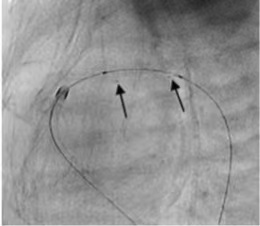

附:手术案例

成功利用IBS Angel?对动脉导管进行开明。术后即刻随访了局显示支架状态结构优良,患者动脉导管内血流畅达。